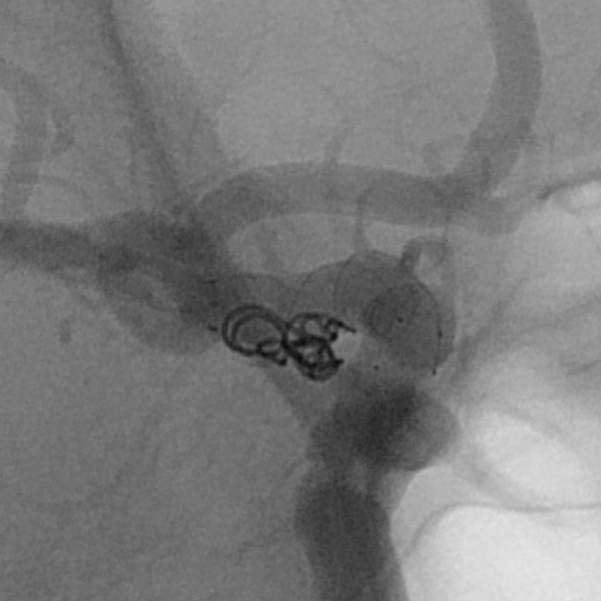

病情变化:中年男性患者,由于头晕查体发现后交通动脉瘤,第一次造影可见形态尚规则,患者及家属经过反反复复的思想斗争,决定采用外科干预。3天后,术中发现动脉瘤的形态已经出现改变,瘤囊的远端出现子瘤。

手术过程:术中采用“一个支架+一个弹簧圈”的简约模式顺利结束手术,消除了动脉瘤破裂出血的风险。

手术结果:本次手术具有“创伤小、花费少、时间短、出院快”的特点,而且支架紧邻分叉部近段,没有覆盖大脑前动脉、支架打开贴壁良好、所有分支保持通畅~~~